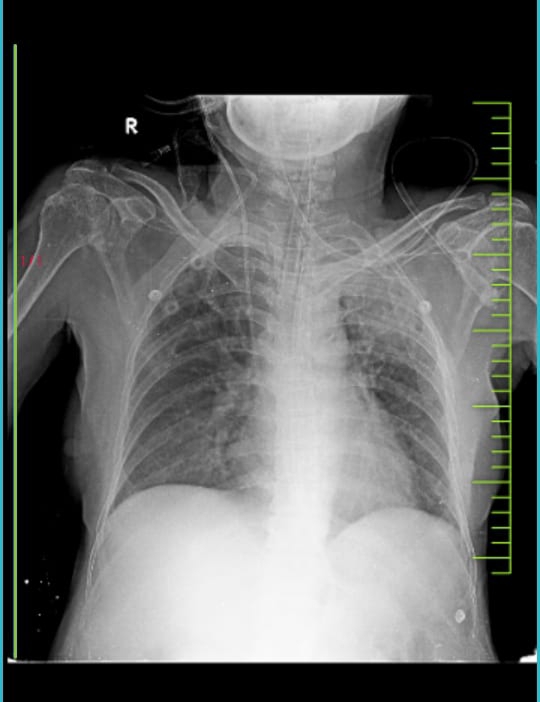

CHEST X RAY

FINAL FIAGNOSIS :

CAD- HEART FAILURE WITH REDUCED EJECTION FRACTION

S/P ON MECHANICAL VENTILATION

CARDIOGENIC SHOCK ? SEPTIC SHOCK

ACUTE PULMONARY EDEMA

SEVERE LV DYSFUNCTION

LEFT UPPER LOBE FUNGAL BALL ?ASPERGILLOMA

DIABETIC KETOACIDOSIS

DIABETIC FOOT ULCER

PSVT- SR

GRADE III  BEDSORE